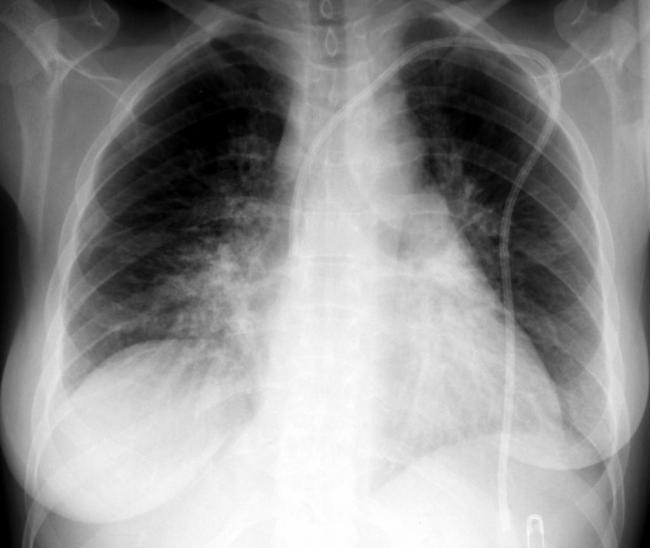

Больной жалуется на одышку. Кожные покровы его бледны; со стороны видимых слизистых может отмечаться синюшность. При аускультации (прослушивании) легких шум дыхания либо ослаблен, либо отсутствует. За счет уменьшения объема легкого при большом ателектазе может быть смещено в сторону поражения средостение; также на стороне поражения может быть высокое стояние диафрагмы. Диагноз подтверждается рентгенологически. Поскольку в закрытом пространстве альвеол присутствуют и развиваются микробы, ателектаз часто осложняется пневмонией.

Диагностика

Клинические симптомы, которые проявляются при ателектазе легкого, не являются специфическими сугубо для этого состояния, поэтому по одной только одышке, учащении сердцебиения и гипотонии заподозрить ателектаз не представляется возможным. Эта симптоматика позволяет заподозрить наличие патологии со стороны органов дыхания в целом, а уточнить ее можно будет при дальнейшем обследовании больного – как физикальном (осмотр, простукивание грудной клетки врачом, выслушивание фонендоскопом), так и с помощью инструментальных методов диагностики.

Опытный врач заподозрит спадание легких на основе осмотра: грудная клетка больного будет ассиметричной при дыхательных движениях – за счет того, что ее пораженная половина не двигается, потому как легкое фактически не дышит (образно говоря, ему нечем дышать).

Во время инструментальных диагностических манипуляций важно не только установить наличие ателектаза и его точную локализацию, но и уточнить объем спавшейся ткани, чтобы определить правильную тактику лечения и объем лечебных манипуляций. На рентгенограмме для диагностики ателектаза имеет значение состояние не только ткани легких, но и корней легких, ребер, органов средостения, купола диафрагмы, плевры, плевральной полости и даже позвоночника (будет наблюдаться его сколиотическое отклонение в направлении выпуклости в сторону пораженного легкого)

На рентгенограмме для диагностики ателектаза имеет значение состояние не только ткани легких, но и корней легких, ребер, органов средостения, купола диафрагмы, плевры, плевральной полости и даже позвоночника (будет наблюдаться его сколиотическое отклонение в направлении выпуклости в сторону пораженного легкого).